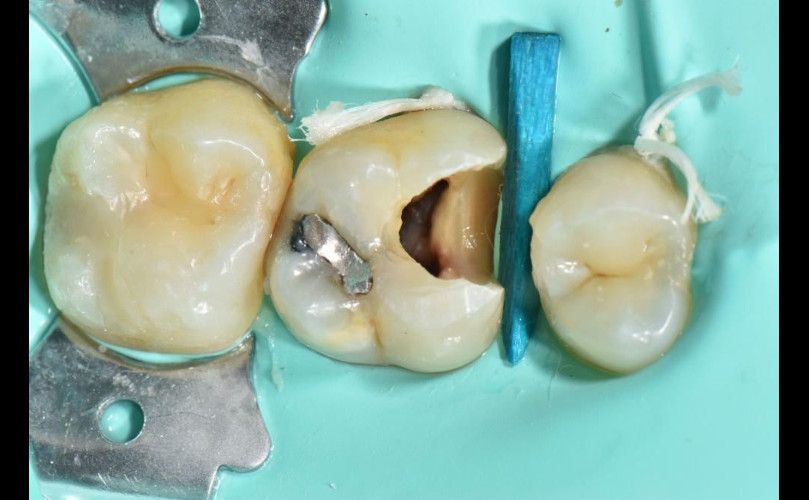

• Anestesiamos, realizamos la apertura y limpieza de la caries y tejido dañado.

• Asilamos el diente del resto y de la boca y saliva, dando un mayor confort al paciente y permitiéndonos trabajar con seguridad y en un espacio totalmente limpio.

• Instrumentemos la, o las raíces hasta su final, mediante el uso de limas de aleaciones muy flexibles que nos permiten trabajar anatomías muy complejas, líquidos desinfectantes, y todo controlado por instrumentos de última generación y radiografías.